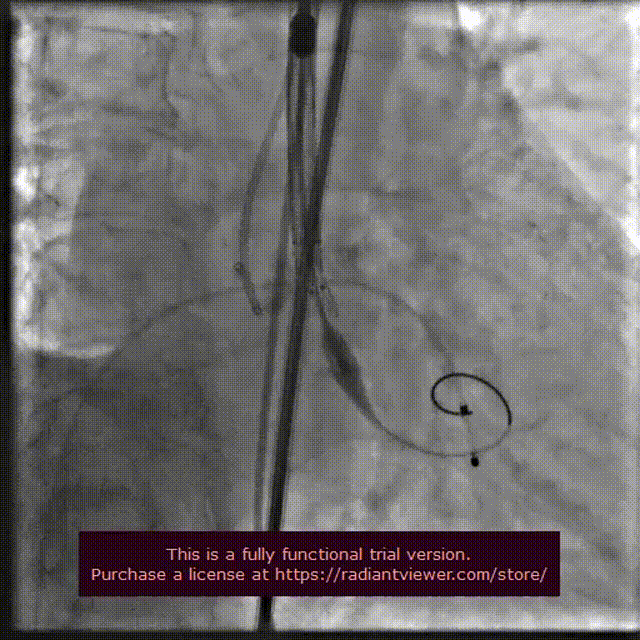

22 mm球囊预扩张

输送系统定位

VenusA-Plus®释放过程

瓣膜完整形态